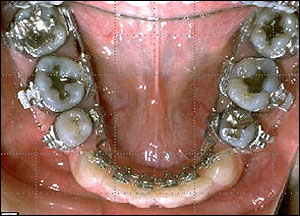

STEP 4. En-mass retraction

Stainless Steel 017*025 (TMA with Closing Loop)